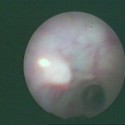

Εικόνες γαλακτοσκόπησης

Εικόνες γαλακτοσκόπησης